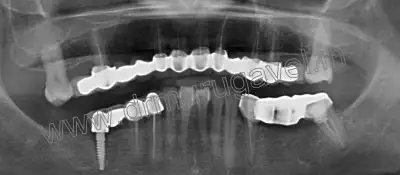

Radiographic examination

OPG and CBCT taken. OPG shows bone loss in upper teeth.. Peri apical radio lucency present in relation to root canal treated 34 and 37 region. And bone loss present in 46 implant region..

Post implant x-ray